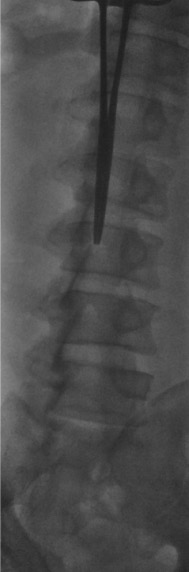

Place patient prone or prone oblique on the fluoroscopy table. Position a pillow under the abdomen to reverse lumbar lordosis and widen the interlaminar spaces. Identify the target interspace (L2–L3 or L3–L4) on fluoroscopy. For oblique positioning, the top leg is bent with arms by the side. Mark the skin entry point under fluoroscopic guidance.

Fluoroscopic approach views

AP fluoroscopic view showing midline approach for lumbar puncture Prone oblique fluoroscopic view showing paramedian approach for lumbar puncture Second prone oblique view showing needle trajectory for lumbar puncture